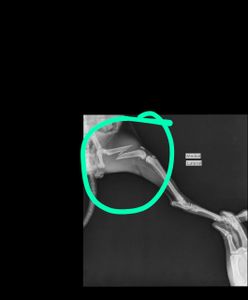

Na manhã seguinte, dia 11/08/2021, levei na clínica veterinária da Unama e fizemos um raio x onde foi identificado uma fratura no fêmur esquerdo. Infelizmente, a clínica da unama não realiza cirurgia ortopédica e foi necessário entrar em contato com um veterinário particular.  Ao repassar o caso, tivemos um orçamento da cirurgia de R$1.600,00, e mais a internação que custa R$120,00 a diária. Entretanto, ao implorar por desconto, consegui a cirurgia por R$1.400,00 á vista ou R$1.600,00 no cartão. Já conseguimos alguns dias de internação grátis, mas necessitamos desse valor para realizar o proedimento e os demais cuidados pós operatório.